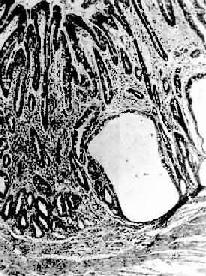

镜 下,病变区腺上皮萎缩,腺体变小并可有囊性扩张,常出现上皮化生(假幽门化生及肠上皮化生)。在粘膜固有层有不同程度的淋巴细胞和浆细胞浸润。在胃体和 胃底部病变区,主要呈现壁细胞消失,其次是主细胞消失和粘液分泌细胞化生。后者称为幽门腺或假幽门腺化生。电镜观察,壁细胞除数量减少外,可见细胞内自噬 泡增多,内质网扩张,高尔基器减少,线粒体肿胀,表面微绒毛消失。内质网、高尔基器和微绒毛是壁细胞的功能部分,其减少或消失反映了细胞泌酸功能的低下或 消失。在幽门窦病变区,主要改变为幽门腺呈不同程度的萎缩、消失(图10-3)并常有肠上皮化生。胃粘膜表层上皮细胞生长,可形成绒毛样突起,增生的上皮 中出现分泌粘液的杯状细胞(图10-4)、具有刷状缘的吸收上皮细胞和Paneth细胞时其形态结构与小肠粘膜相似,故称为肠上皮化生。现知肠上皮化生的 胃粘膜易诱发胃癌,多为息肉腺癌

慢性萎缩性胃炎

图10-3 慢性萎缩性胃炎

幽门腺大部分萎缩消失,胃小凹延长,有潴留性小囊形成,腺上皮中杂有不少杯状细胞(肠上皮化生),固有膜内有不少慢性炎性细胞浸润(Ⅱ74-4950)